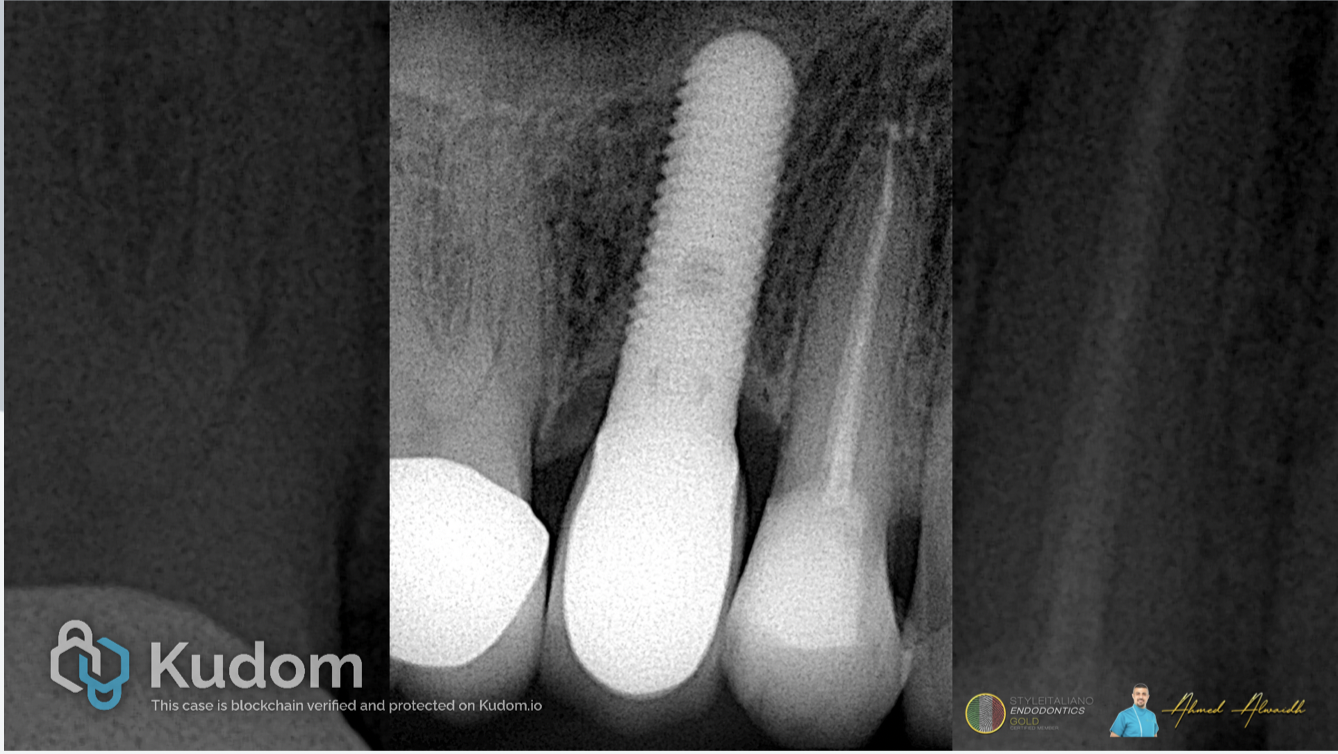

Fig. 6

Post-operative IOPA. The patient been sent for his RD for definite cuspal coverage